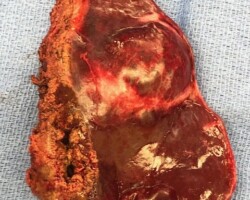

Resection of large retroperitoneal sarcoma including right and transverse colectomy and right hepatectomy